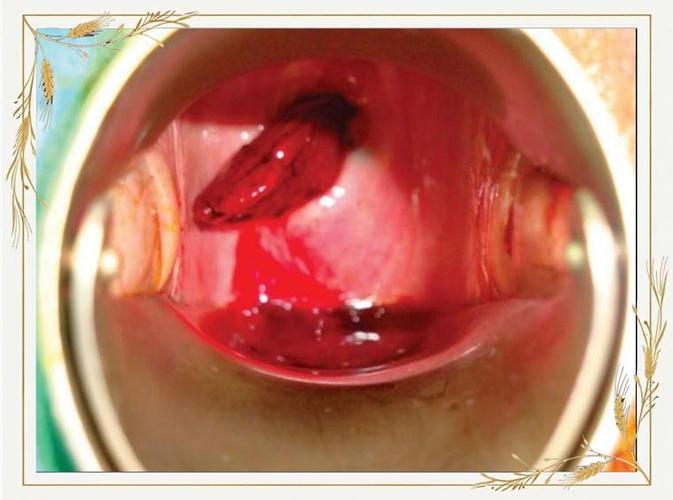

宫颈息肉是宫颈管内或宫颈口表面的良性赘生物,通常由宫颈管内膜的腺体和间质增生形成,它看起来像一个小小的、肉色的、带蒂的“小肉芽”,质地柔软,触碰容易出血。

- 在每次产检时,医生会通过窥器检查观察息肉的大小、形态和有无出血。